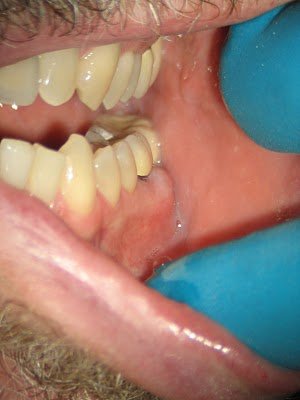

The tooth is deemed non-restorable and extraction recommended.

If you are unsure if a tooth has a cracked/fractured root, contact your endodontist. Not all teeth can be saved, but endodontists are the specialists for saving teeth and can help you determine which ones to save.